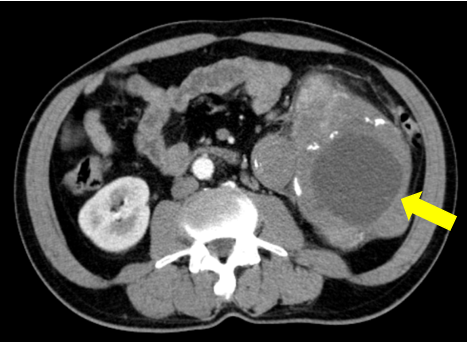

- Chụp cắt lớp vi tính ổ bụng: Vùng mạn sườn trái có tổn thương kích thước ~ 108x114x130mm, tỷ trọng hỗn hợp gồm phần dịch trung tâm và phần đặc, kèm vài nốt vôi hóa rải rác, phần đặc ngấm thuốc không đồng nhất sau tiêm, thâm nhiễm xung quanh. Tổn thương đè đẩy thận trái lên trên, vào trong, có phần ranh giới không rõ với thận trái.

Hình 1: Hình ảnh chụp cắt lớp vi tính bụng: u vùng mạn sườn trái có tổn thương tỷ trọng hỗn hợp kèm vài nốt vôi hóa rải rác, thâm nhiễm xung quanh (mũi tên vàng).